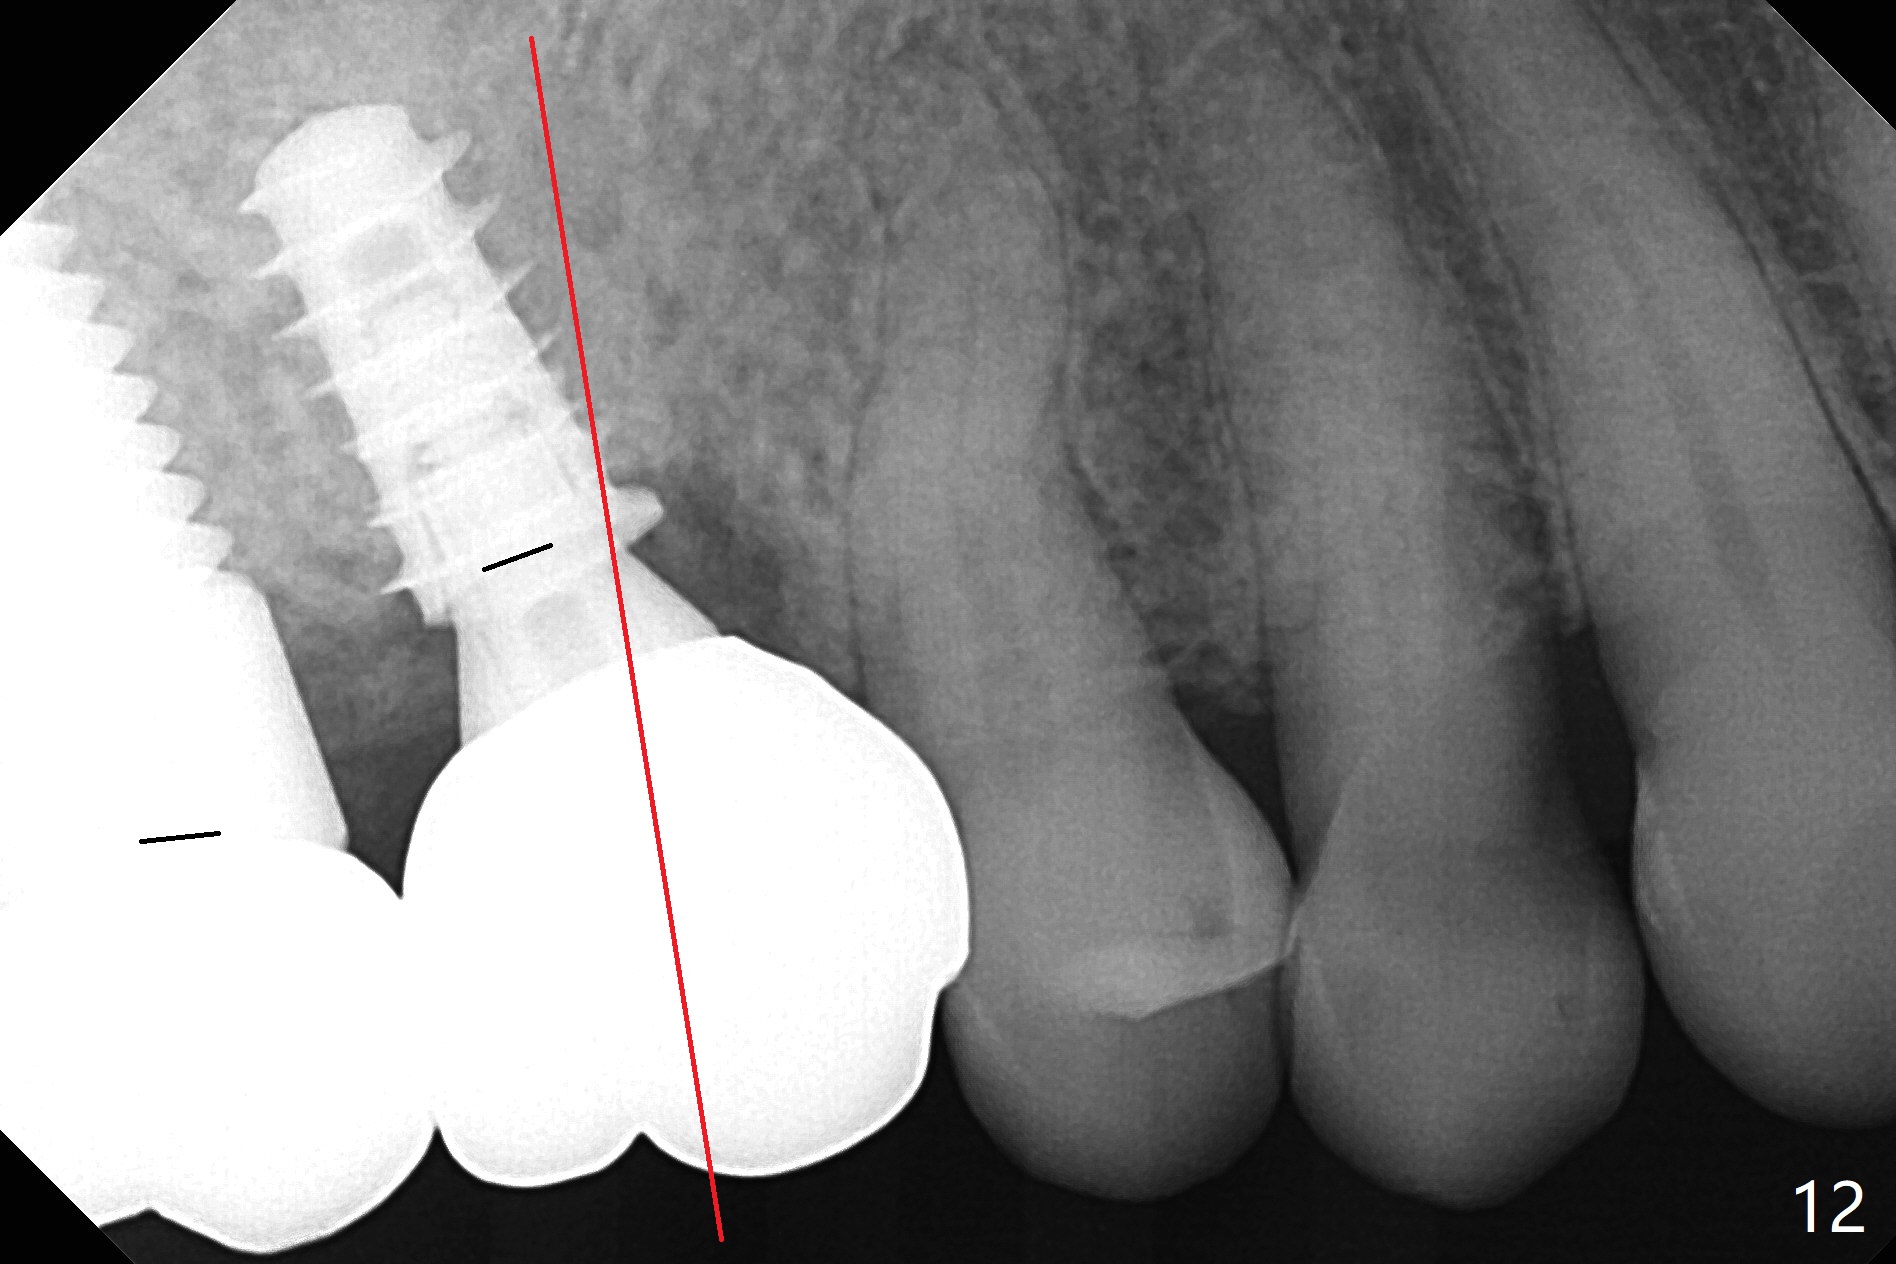

The abutment screw is loose 2.5 months post cementation (Fig.12), but the bone density in the previous mesiobuccal and distobuccal sockets increases. The patient chews crab leg. The other two contributing factors to screw loosening are poor trajectory (as compared to the long axis (red line)) and poor crown/implant ratio associated with the bone-level implant as compared to that in the tissue-level one (at #2). It appears appropriate to choose the latter for a bruxer. Take PA as early as possible in osteotomy to determine trajectory.